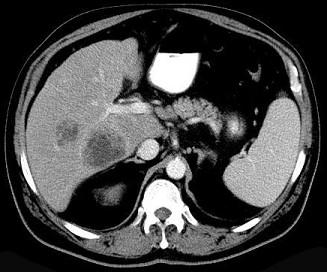

问题 细菌性肝脓肿的最常见致病菌是 ( )

选项 A、粪链球菌、金黄色葡萄球菌和厌氧菌 B、溶血性链球菌、金黄色葡萄球菌和厌氧菌 C、大肠杆菌、粪链球菌和厌氧菌 D、大肠杆菌、金黄色葡萄球菌和厌氧菌 E、大肠杆菌、绿脓杆菌和厌氧菌

答案 D